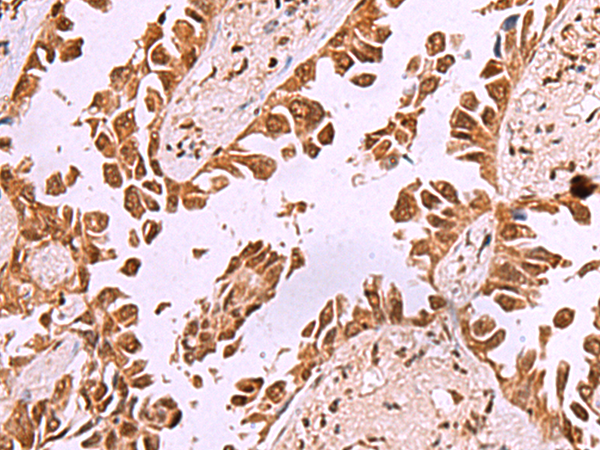

ELISA, WB, IHC

IHC positive control:

Human lung cancer and Human ovarian cancer

IHC Recommend dilution:

40-200